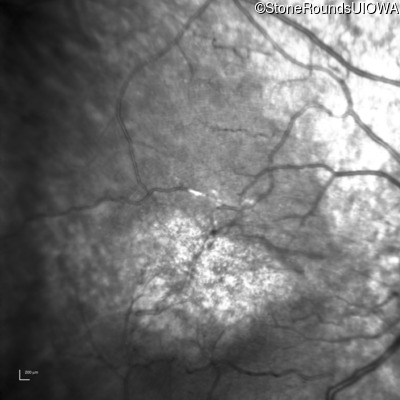

Infrared Fundus Photograph - Right - 20/160

Exemplar